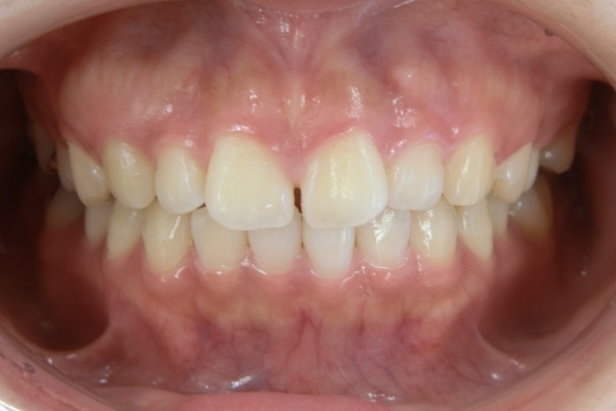

AFTER

治療はマウスピース矯正で行い、治療期間はわずか1年で歯並びが整いました。さらにホワイトニングも併用したことで、歯並びだけでなく歯の色も明るくなり、整った歯並びと白い歯が調和した、より印象的な口元へと改善しています。

治療後は、周囲の方から歯を褒められることが増え、笑顔に自信が持てるようになったとお話しくださり、「本当に矯正してよかった」と、現在もメインテナンスで通院されるたびに嬉しいお言葉をいただいています。また、お子さまのうちお二人も、同じマウスピース矯正で現在当院にて治療を進めており、ご家族で通っていただいている症例です。

| 施術内容 | 歯全体のマウスピース矯正システム「インビザラインライト」を用いた治療 |

| 治療期間 | 1年 |

| 費用 | 528,000円 |

| リスク/副作用 | 全ての方で、疼痛、咬合痛、歯根吸収、歯肉退縮、歯髄壊死が生じる可能性があります。 |

| その他注意点 | 指定した時間、マウスピースをつけていただけない場合は治療期間が長くなる場合があります。 |